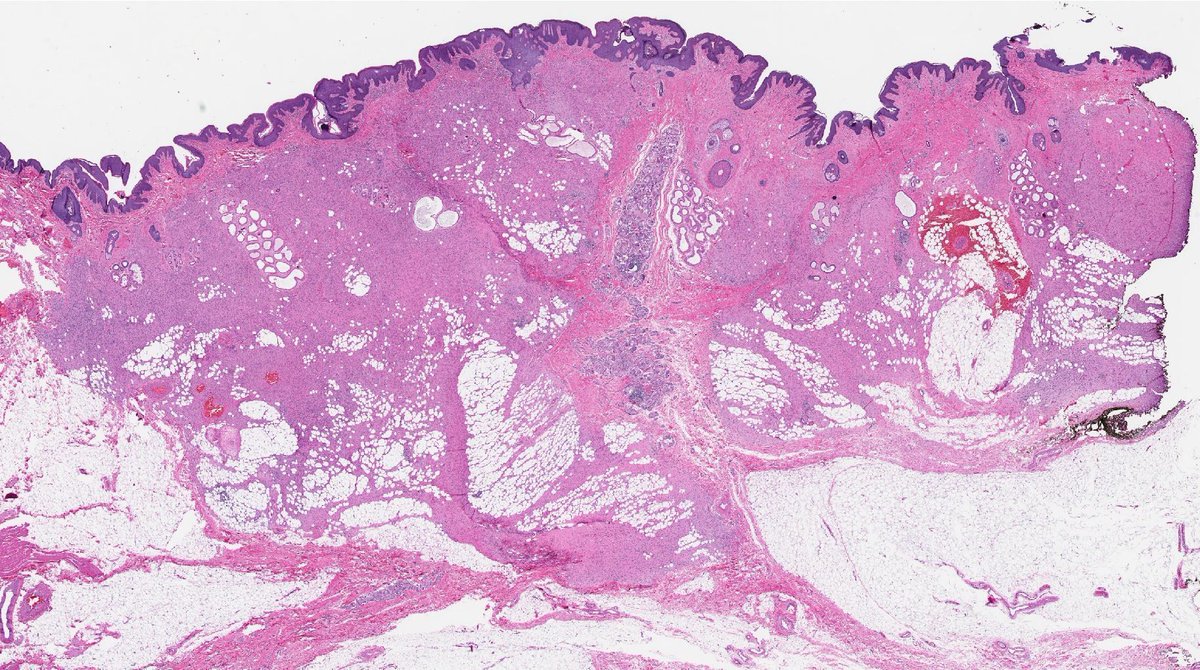

20 yo F. Bilateral groin excisions. Diagnosis? Digital slides: kikoxp.com/posts/8027 Answer ✅ youtu.be/Zy07nO1VuiY?si… #pathology #pathologists #pathTwitter #dermpath #dermatology #dermatologia #dermtwitter

20 yo F. Bilateral groin excisions. Diagnosis?

Digital slides: kikoxp.com/posts/8027

Answer ✅ youtu.be/Zy07nO1VuiY?si…

#pathology #pathologists #pathTwitter #dermpath #dermatology #dermatologia #dermtwitter